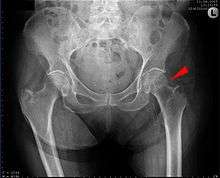

![]() AP hip radiograph demonstrating an intertrochanteric fracture | |

X-rays of the affected hip usually make the diagnosis obvious; AP (anteroposterior) and lateral views should be obtained.